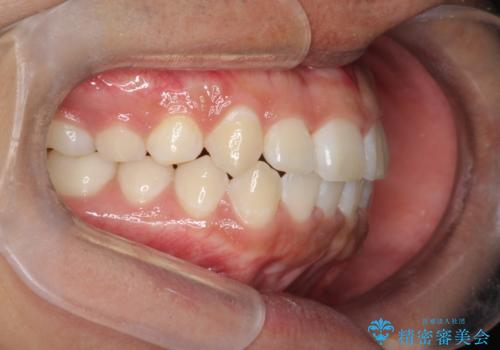

前歯のガタガタを目立たずきれいにしたい インビザラインによる見えない矯正

- 前歯のがたつきを主訴に来院されました。

上顎の前から2番目の歯の噛み合わせが反対になっていました。

抜歯矯正も考えられるケースでしたが、非抜歯での矯正を希望され、インビザラインにて治療することとなりました。

目立たずに矯正を終えることができ、患者様にも満足していただきました。